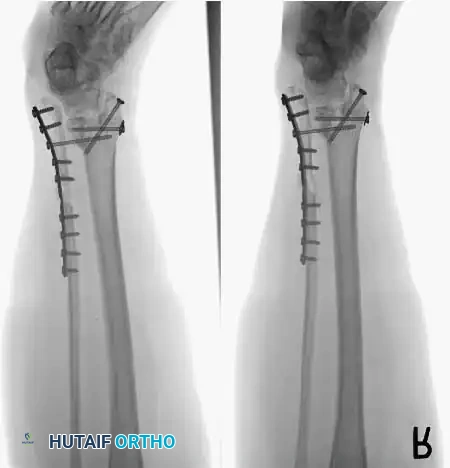

Internal fixation is currently the preferred method for uncomplicated ankle arthrodesis due to higher union rates, superior patient comfort, and the elimination of pin-tract infections. Biomechanical studies demonstrate that crossed, large-diameter (6.5 mm or 7.3 mm) cannulated cancellous screws provide exceptional resistance to shear and torsional forces.

A standard construct involves two or three screws:

1. A "home run" screw directed from the posterior malleolus into the anterior neck of the talus.

2. A screw from the medial malleolus into the lateral body of the talus.

3. A screw from the anterolateral tibia into the medial talar body.

In cases of severe osteopenia or when extending the fusion to the subtalar joint (Tibiotalocalcaneal Arthrodesis), retrograde intramedullary nailing provides a load-sharing construct with superior bending stiffness.

For complex hindfoot reconstructions, specialized plating systems, including anterior or lateral locking plates, can be utilized to supplement screw fixation, particularly when structural allografts are required to restore limb length.